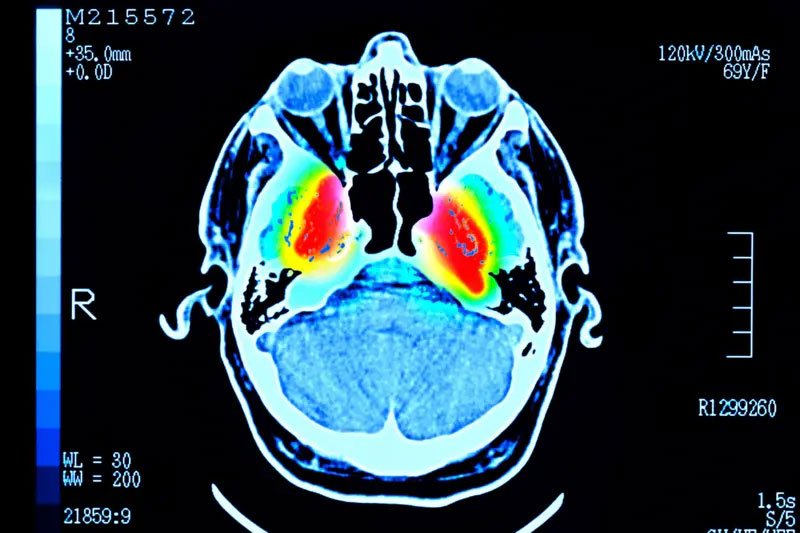

در این مطالعه حدود چهار هزار نفر تا سن ۹۰ سالگی تحت اسکن مغزی قرار گرفتند تا ارتباطات میان سلولهای مغزی آنها مشخص شود.